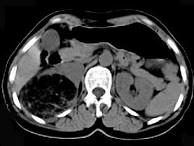

问题 女,53岁,右侧轻度腰背酸痛,行CT检查,如图所示,可能的诊断为()

选项 A.右肾上腺髓样脂肪瘤 B.右肾上腺腺瘤 C.右肾上腺嗜铬细胞瘤 D.右腹膜后脂肪瘤 E.右肾血管平滑肌脂肪瘤

答案 A